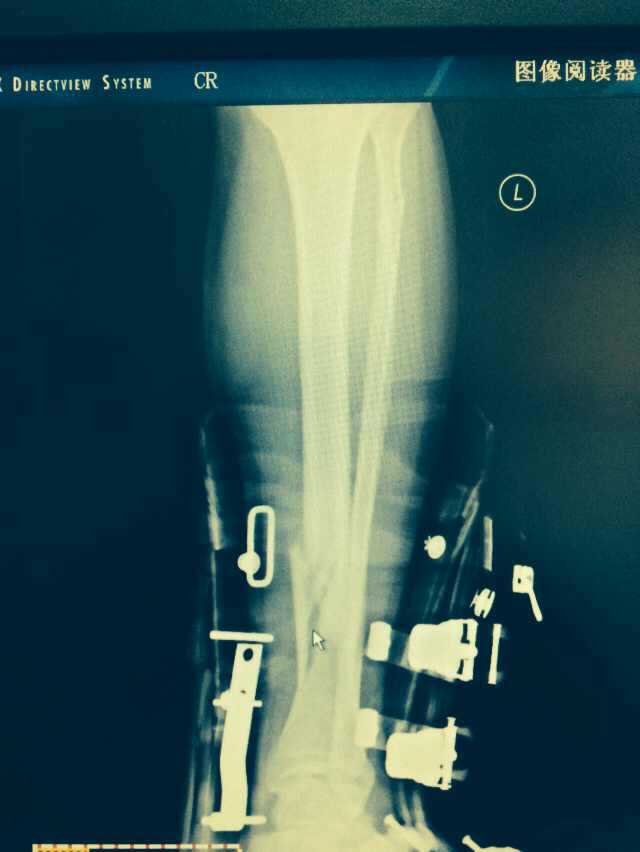

【byb.cn 】(來(lái)源:綜合)2014年12月18日,現(xiàn)年57歲的著名體育評(píng)論員韓喬生,在崇禮云頂滑雪場(chǎng),騎行德國(guó)雪上自行車的時(shí)候,因速度太快,控制不住,韓喬生為避免沖下路基,與一滑行單板的美女相撞,美女因裝備厚,無(wú)大礙,韓喬生則導(dǎo)致左腿脛骨、腓骨兩外骨折,后已經(jīng)被緊急送往北京的醫(yī)院治療。